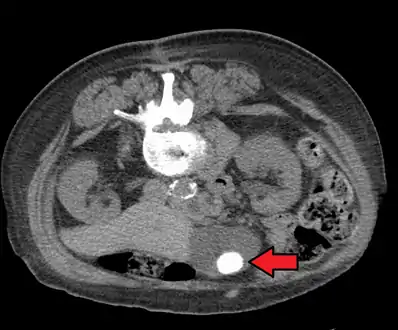

Large gallstone as seen on CT- A normal gallbladder on ultrasound with bowel peristalsis creating the false appearance of stones